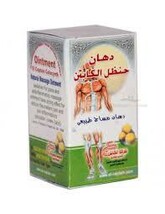

12 pcs Captain Colocynth Balm Muscle Pain and 48 similar items

12 pcs Captain Colocynth Balm Muscle Pain Relief Herbal Ointment 12 pcs x 50mg

12 pcs Ointment El captain Colocynth Handal Herbal Muscle Pain Massage Relief Weight: 50 gm= ( 1.76 oz ) - Material: The Fresh Colocynth - Eucalyptus Globulus - Cumin Extract - Gaultheria - Fennel Extract - Eugenol - Natural Mint Extract - Carvhon Limonin Sedative For Pains Ointment Has Strong Effect , Suitable for reducing muscle pain, joint pain, back pain and soft tissue After the ointment has been applied, muscles will relax. Also recommended to be used as a sports ointment. Ideally suited to people who engage in rehabilitative sports. Production and expiration dates are indicated on the original packaging in the European format MM/YY